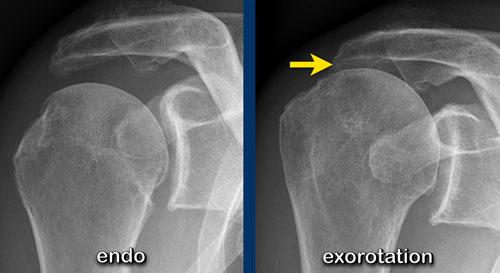

Bệnh nhân này có khoang dưới mỏm cùng vai bị hẹp.

Lưu ý rằng tình trạng hẹp được thấy rõ trên hình chụp vai ở tư thế xoay ngoài, trong khi không quan sát được trên hình chụp ở tư thế xoay trong.